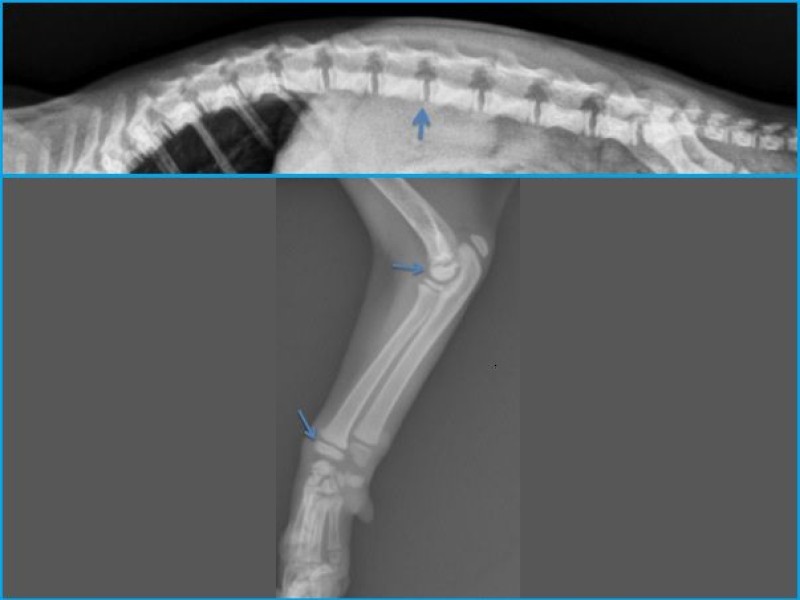

Des radiographies du squelette révèlent un retard d'ossification des épiphyses de manière symétrique et généralisée. Les os du carpe sont absents.

Une radiographie d'un châton de la portée et du même âge a été prise en comparaison. Cf la deuxième radio.

Discussion: Des anomalies du squelette, comme un retard de maturation et une dysgénésie épiphysaire sont caractéristiques d'une hypothyroïdie congénitale, plus tard les animaux ressemblent à des nains disproportionnés.

Un retard de maturation épiphysaire est observée dans les

corps vertébraux et les os longs des chatons, accompagné d'un retard de maturation des os du carpe et du tarse. La dysgénésie épiphysaire se caractérise par un délai d'apparition des foyers d'ossifications épiphysaires, et en absence de supplémentation, les épiphyses apparaissent fragmentées avec des foyers de minéralisation dispersés. Normalement, les épiphyses se développe d'un centre unique. Plus tard, cette malformation hypophysaire conduit à des arthropathies dégénératives.